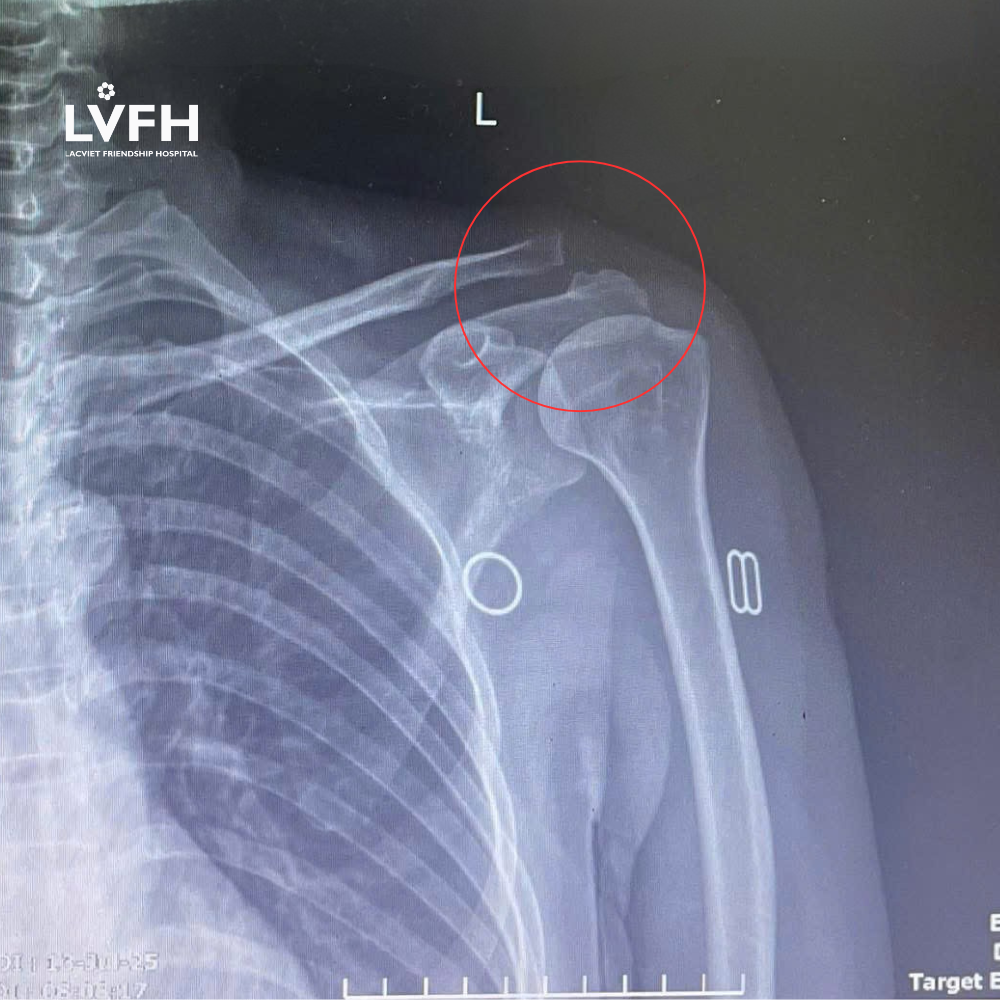

Bệnh nhân nữ, 43 tuổi, có tiền sử tai nạn giao thông cách nhập viện 3 tuần, được chẩn đoán chấn thương cột sống, xẹp đốt sống L3 và trật khớp cùng đòn trái. Sau khi điều trị bảo tồn ổn định cột sống, người bệnh vẫn còn đau nhiều vùng khớp vai trái.

Sau khi được thăm khám chuyên sâu và tư vấn kỹ càng, các bác sĩ Bệnh viện Lạc Việt đã chỉ định phẫu thuật nội soi cố định khớp cùng đòn trái.

- Khớp cùng đòn trở lại vị trí bình thường